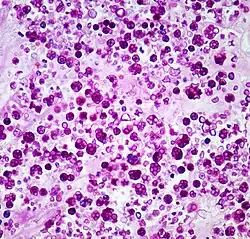

| Histologic stain of a Prototheca zopfii infection in a dog | |

Protothecosis, otherwise known as Algaemia, is a disease found in dogs, cats, cattle, and humans caused by a type of green alga known as Prototheca that lacks chlorophyll and enters the human or animal bloodstream. It and its close relative Helicosporidium are unusual in that they are actually green algae that have become parasites.[1] The two most common species are Prototheca wickerhamii and Prototheca zopfii. Both are known to cause disease in dogs, while most human cases are caused by P. wickerhami.[2] Prototheca is found worldwide in sewage and soil. Infection is rare despite high exposure, and can be related to a defective immune system.[3] In dogs, females and Collies are most commonly affected.[4]

Prototheca has been thought to be a mutant of Chlorella, a type of single-celled green alga. However, while Chlorella contains galactose and galactosamine in the cell wall, Prototheca lacks these. Also, Chlorella obtains its energy through photosynthesis, while Prototheca is saprotrophic, feeding on dead and decaying organic matter. When Prototheca was first isolated from slime flux of trees in 1894, it was thought to be a type of fungus.[6] Its size varies from 2 to 15 micrometres.[7]

Disseminated protothecosis is most commonly seen in dogs. The algae enters the body through the mouth or nose and causes infection in the intestines. From there it can spread to the eye, brain, and kidneys. Symptoms can include diarrhea, weight loss, weakness, inflammation of the eye (uveitis), retinal detachment, ataxia, and seizures.[11]

Dogs with acute blindness and diarrhea that develop exudative retinal detachment should be assessed for protothecosis.[6] Diagnosis is through culture or finding the organism in a biopsy, cerebrospinal fluid, vitreous humour, or urine. Treatment of the disseminated form in dogs is very difficult, although use of antifungal medication has been successful in a few cases.[4] Prognosis for cutaneous protothecosis is guarded and depends on the surgical options. Prognosis for the disseminated form is grave. This may be due to delayed recognition and treatment.[3]